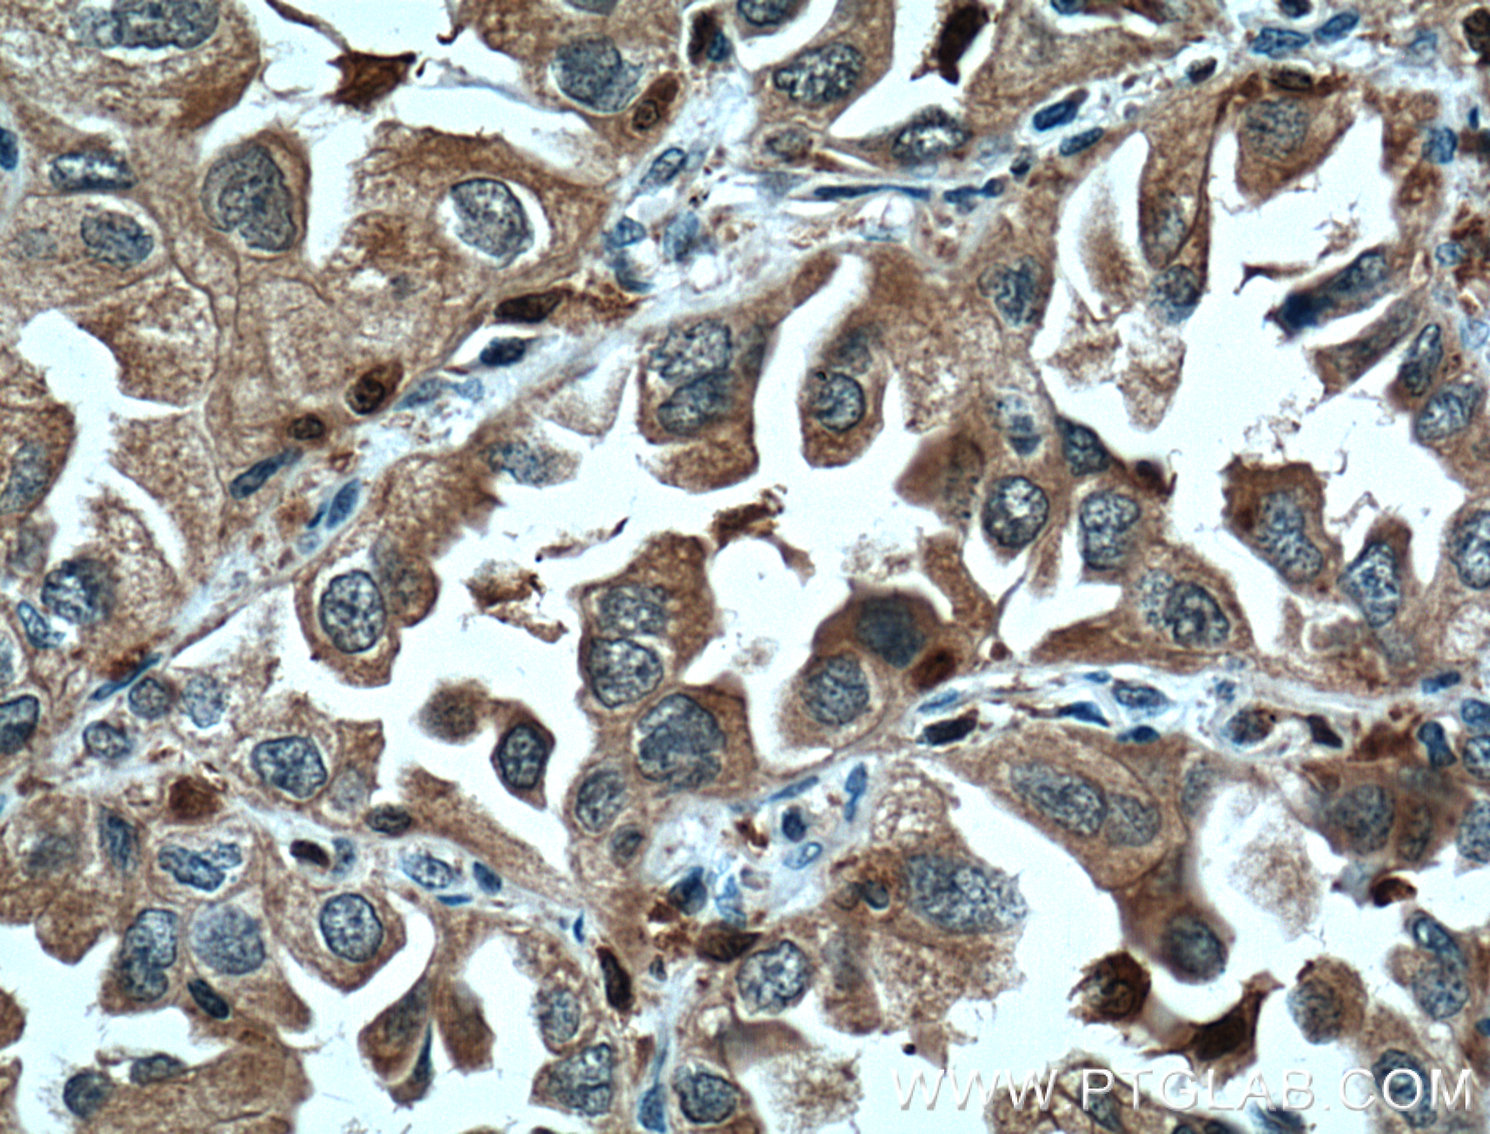

| Positive IHC detected in | human lung cancer tissue Note: suggested antigen retrieval with TE buffer pH 9.0; (*) Alternatively, antigen retrieval may be performed with citrate buffer pH 6.0 |

| Immunohistochemistry (IHC) | IHC : 1:50-1:500 |